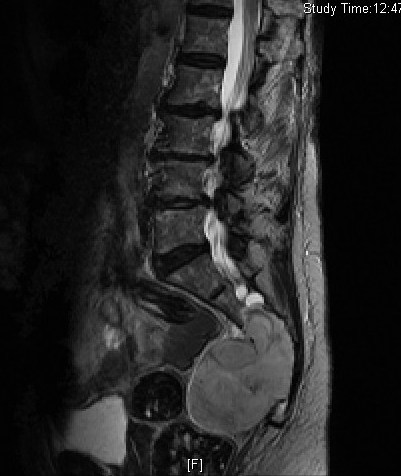

MRI (Fig. 4-10)

• Isointense or hypointense on T1W (Fig. 4-5)

• Hyperintense on T2W (Fig. 8 & 9)

• Hyper enhancement with gadolinium (Fig. 6 & 7).

Fig. 4-10: MR image of a chordoma shows a destructive bone lesion in the sacrum that is hypointense on T1W images, hyperintense signal on T2W and enhancement of the lesion after gadolinium.